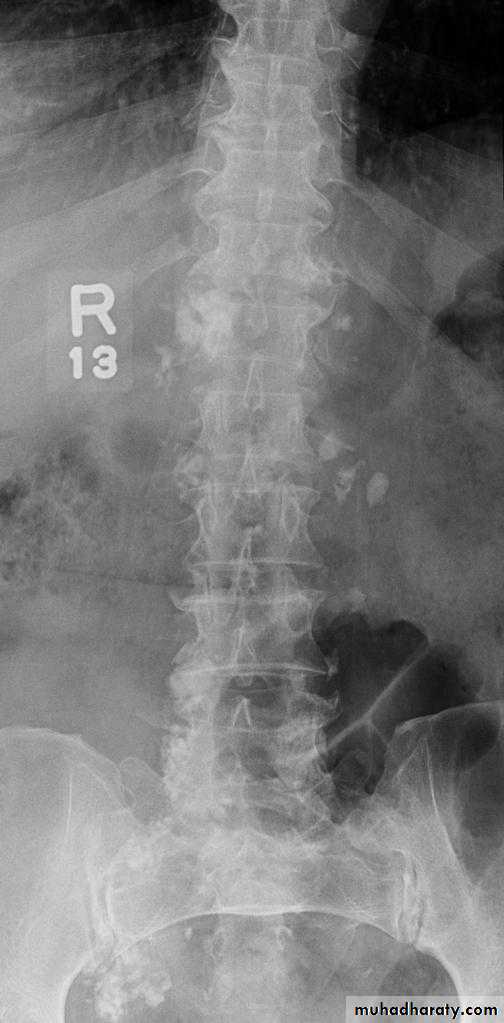

-Over 90% of calculi are radiopaque on plain films and virtually all on CT as very sensitive for detection of calculi, even those that appear radiolucent on plain film.-Most of these stones are a mixture of calcium oxalate and phosphate.

-Only pure uric acid and xanthine stones are radiolucent on plain x-ray but CAN be identified by CT or US, uric acid stones are associated with increased uric acid excretion in urine as in gout.

• Ddgx of stone on KUB :

• 1. Gall stone• 2. calfied LN , cartilage ,fibroid,

• 3. Phlebolith: round, lucent centre.

Schistosomiasis

Infestation by s.hematobium

Calcification is most important feature, mainly in bladder & lower ureters , but may involve whole ureters .

In early stage inflammation may cause cobble stone appearance.

Bladder capacity not affected.Ddgx of bladder calcification :

1. schistosomiasis .2.tumor , TB, …